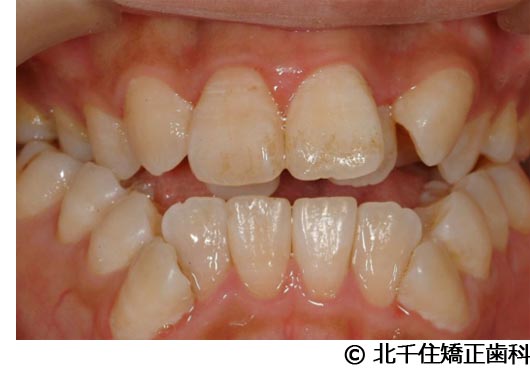

【症例2】上顎前突症

- 治療前

- 治療中

- 治療後

- 治療名

- 上顎前突症

- 費用

- 1,399,000円(税込)

- 期間

- 3年6ヵ月

- 治療回数

- 42回

- 通院頻度

- 1ヵ月ごと

- 年齢・性別

- 19歳10ヵ月・男性(初診時)

治療内容

-

患者様の症状

主訴:出っ歯、口元の突出、横顔をきれいにしたい

治療方法

骨格性の上顎前突、上下顎第一小臼歯4本及び上顎第二大臼歯を抜歯して矯正用アンカースクリューを併用してワイヤー矯正治療(セラミックブラケット)。

治療結果

骨格性上顎前突に対し、抜歯および矯正用アンカースクリューを併用した矯正治療により歯列および咬合関係の調整を行った症例である。治療後は保定装置を使用し、歯列および咬合の安定維持を目的として定期的な経過観察を行っている。

※治療結果は個人差があります。

治療を行う上での注意点(リスク・副作用)

歯磨き不良に伴うカリエスや歯周病、顎関節症、歯根吸収など。